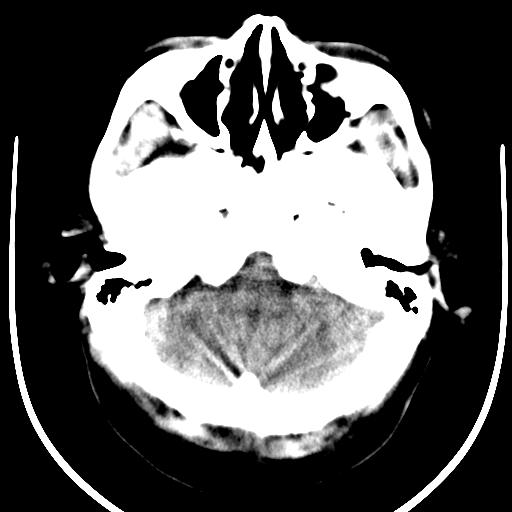

女42岁,从7岁开始就出现癫痫,至今症状不缓解,近几年做过好几次ct 检查,影像上改变不明显。。

癫痫的特征是大脑神经元反复发作的异常放电,导致的暂时性大脑功能失调。该图可见右侧颞叶一不规则软化区。不排除胶质细胞瘤的可能性。应进一步检查脑电以定位,做核磁或穿刺以确诊。

本病例病程较长,并侧裂池明显扩大,周围见低密度影及内见条片状钙化灶。多考虑:“蛛网膜囊肿或脑裂畸形”伴“血管畸形”!